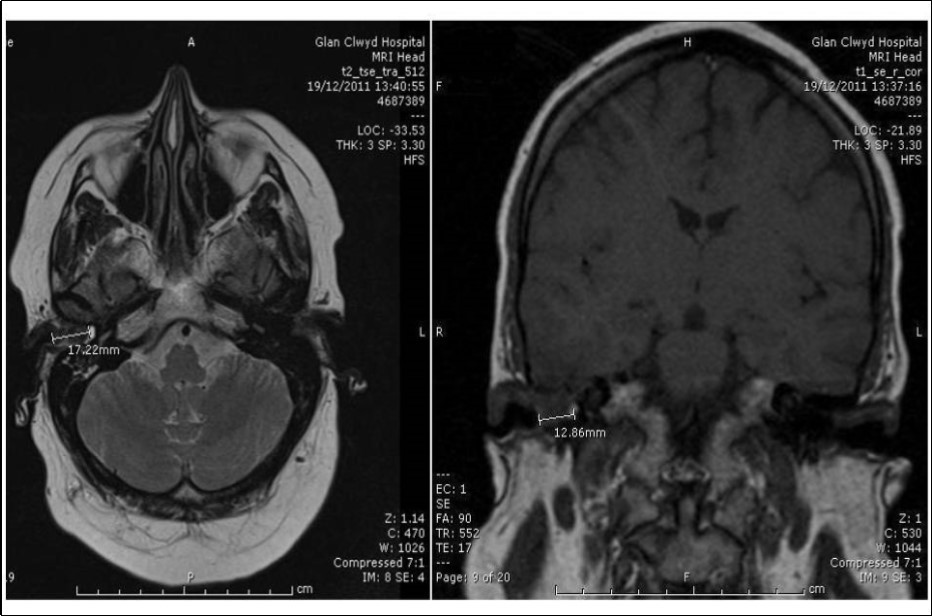

She had CT and MRI of her head. The CT showed occlusion of right external auditory canal with soft tissue mass with bone destruction superiorly. The soft tissue pushed the tympanic membrane into the middle ear which was itself pneumatised and free of the disease (Figure 3). The MRI detected intracranial extension into posterior fossa (Figure 4). She had also CT scan of neck, thorax, abdomen and pelvis for staging that didn’t show further disease.

Figure 4.Axial MRI head showing extension from medial aspect of right EAC intracranially